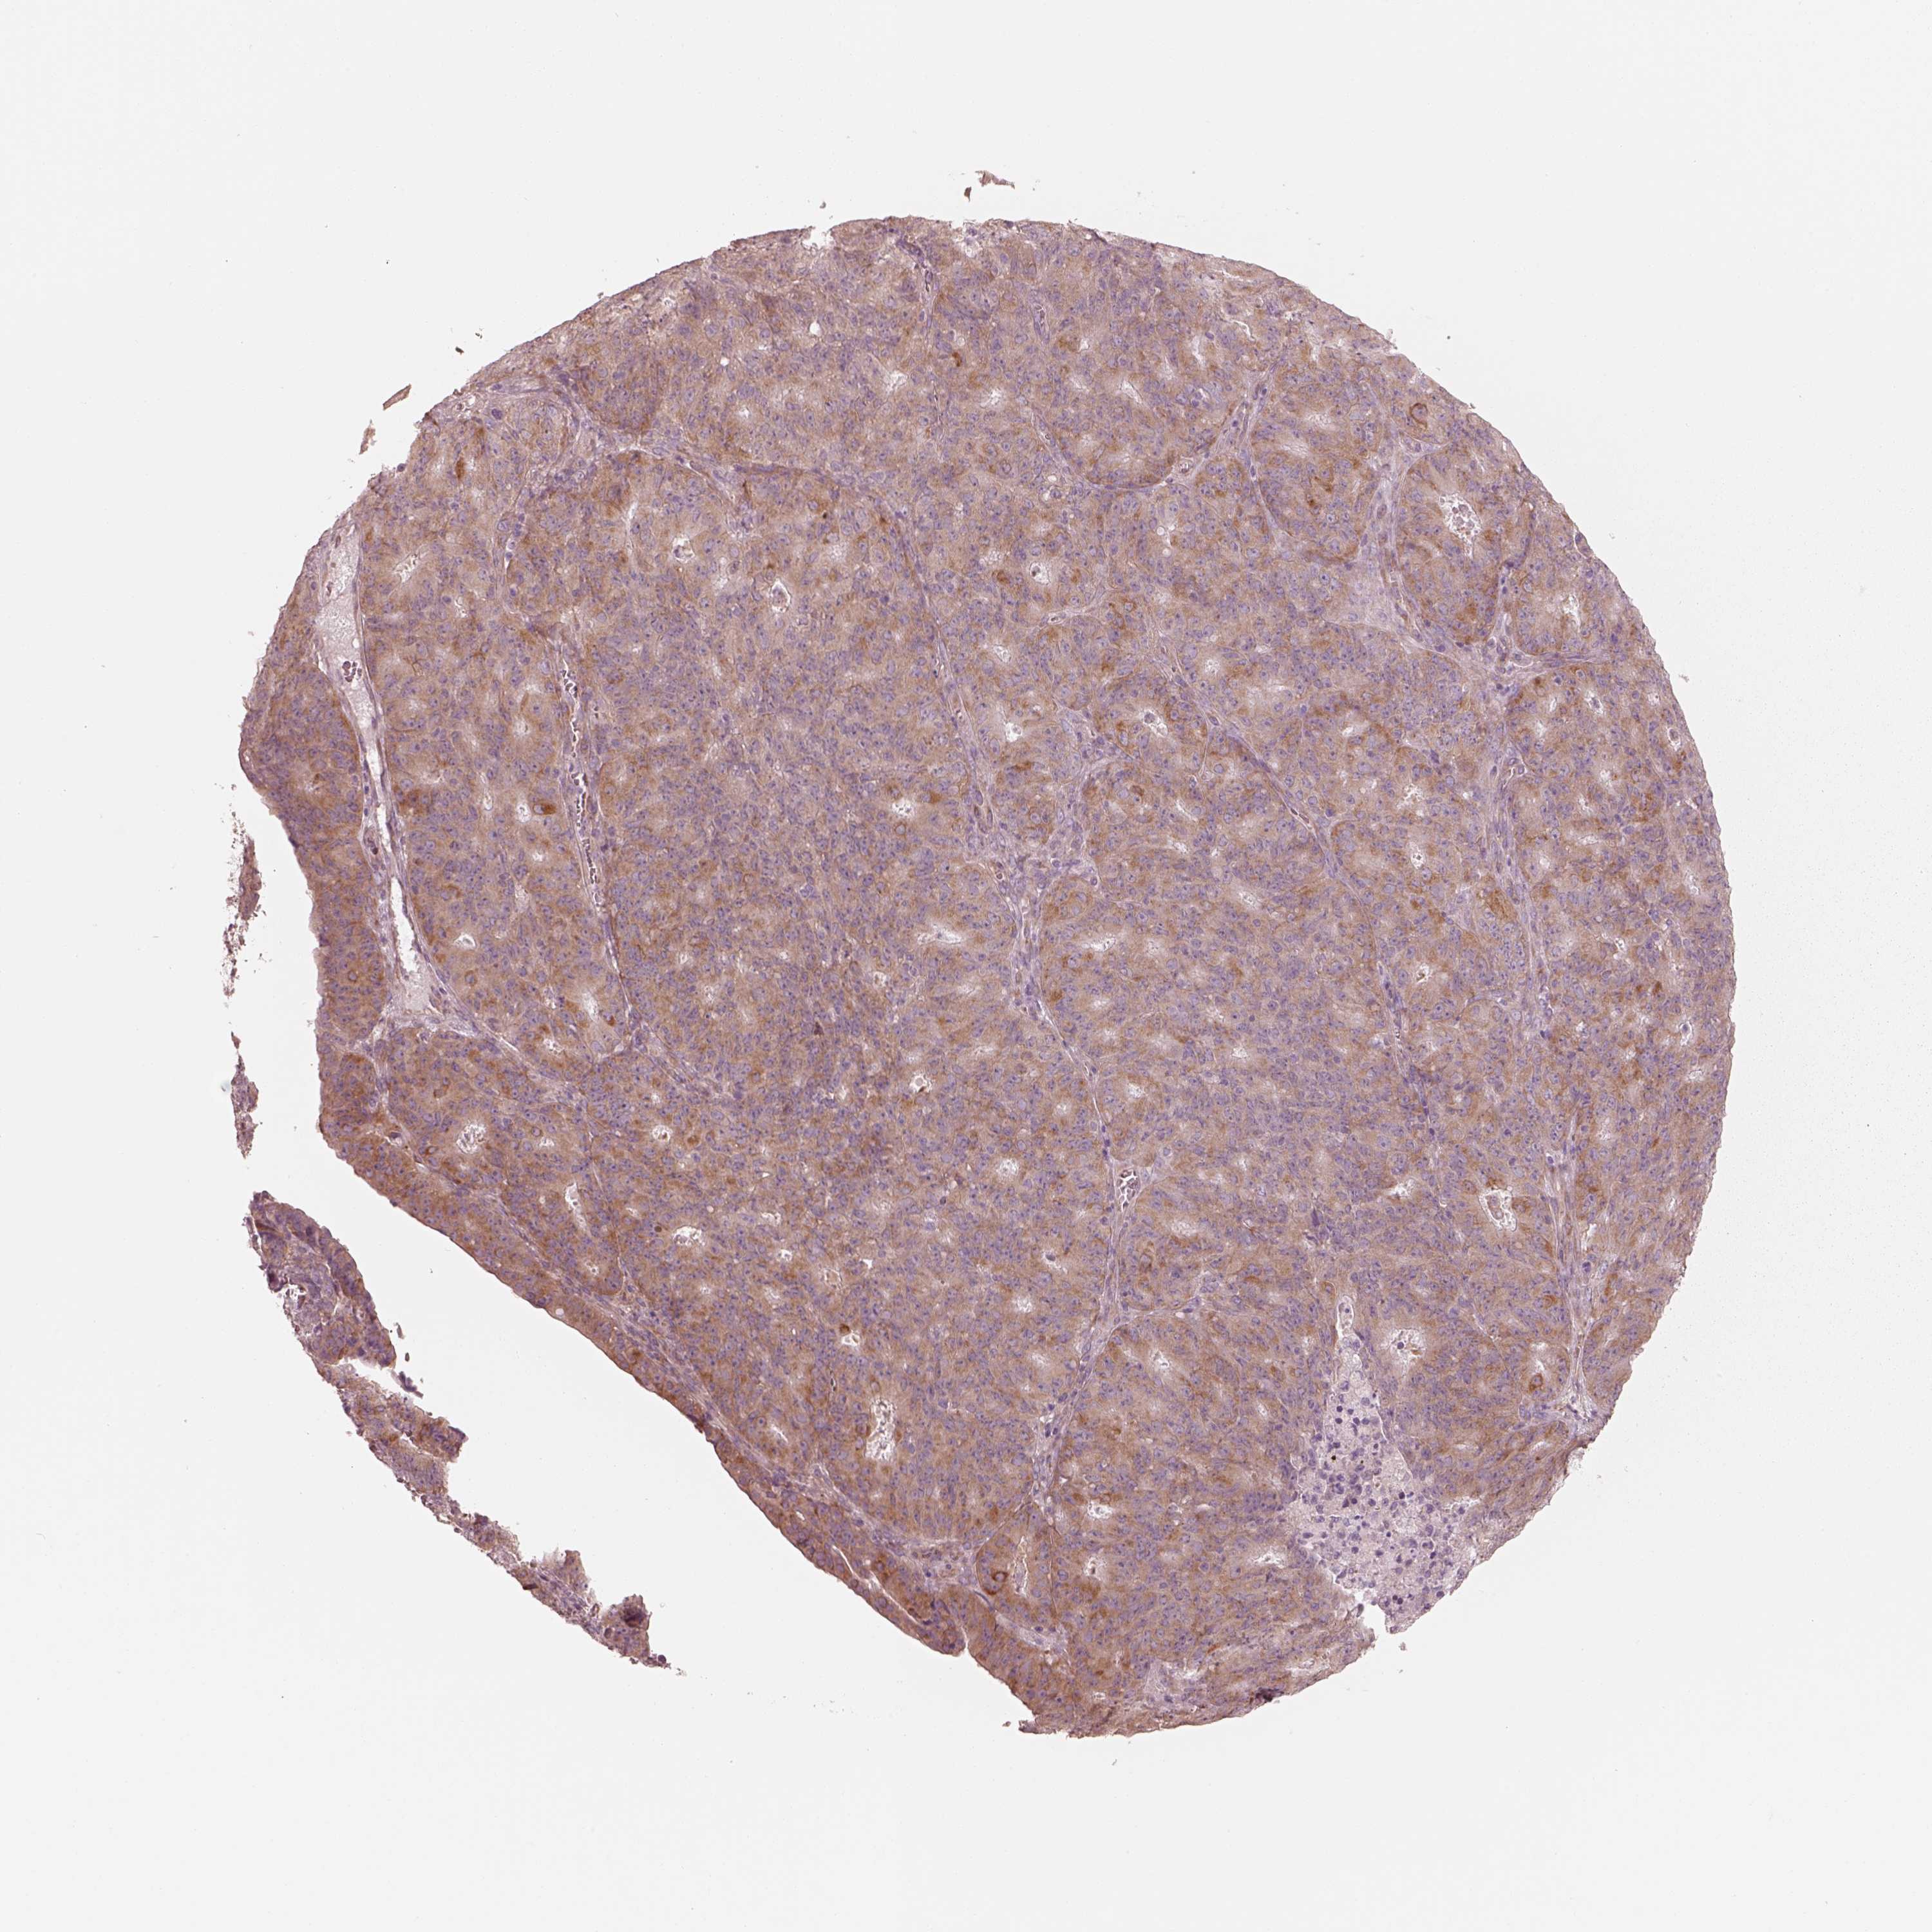

OVARIAN CANCER - Protein expressioni

A mouse-over function shows sample information and annotation data. Click on an image to view it in a full screen mode. Samples can be filtered based on level of antibody staining by selecting one or several of the following categories: high, medium, low and not detected. The assay and annotation is described here.

Note that samples used for immunohistochemistry by the Human Protein Atlas do not correspond to samples in the TCGA dataset.

Antibody stainingi

Antibody staining in the annotated cell types in the current human tissue is reported as not detected, low, medium, or high, based on conventional immunohistochemistry profiling in selected tissues. This score is based on the combination of the staining intensity and fraction of stained cells.

Each image is clickable and will lead to virtual microscopy that enables deeper exploration of all samples and also displays staining intensity scores, fraction scores and subcellular localization as well as patient and tissue information for each sample.

Antibody HPA003160

Antibody HPA048156

Cystadenocarcinoma, mucinous, NOS

Carcinoma, endometroid

Cystadenocarcinoma, serous, NOS